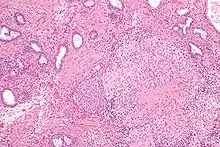

عُصية كالميت غيران كما تعرف باختصارها بي سي جي (Bacillus Calmette–Guérin BCG) وهو لقاح ضد الـسل و يستخدم كعلاج لبعض سرطانات المثانة.

يتم تحضير اللقاح من الذرية الموهنة (مضعفة الفوعية) لعصية السل البقري الحية (المتفطرة البقرية) التي فقدت فوعيتها في الإنسان. تسعى العُصية الحية للاستغلال الأمثل للغداء المتوفر لها، ولذلك فعندما تدخل مضيفًا بشريًا تصبح أقل تكيفا في دم الإنسان وتفقد قدرتها على إحداث مرض. ومع ذلك فالعصيّة تشبه أسلافها البرية في توفير درجة من المناعة ضد السل البشري. فعالية لقاح بي سي جي تتفاوت من 0٪ وحتى 80٪ في منع السل (الدرن) لمدة 15 عاما. ومع ذلك يظهر أن تأثير الحصانة يختلف تبعا للمنطقة الجغرافية والمعمل الذي نمت فيه الذرية.[1]